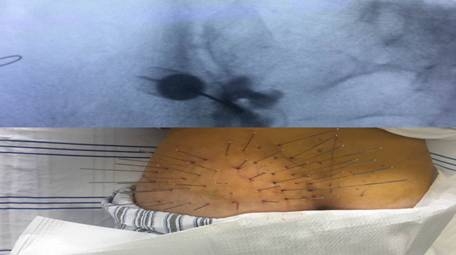

根据查体、病史收集、辅助检查及分析讨论,冯女士最终被确诊为:左骶髂关节炎。医生给予消炎止痛,缓解肌肉痉挛,中药外敷等治疗,并在局麻下施行内热针治疗术+左骶髂关节射频+阻滞术,手术效果极其良好!

冯女士治疗过程中